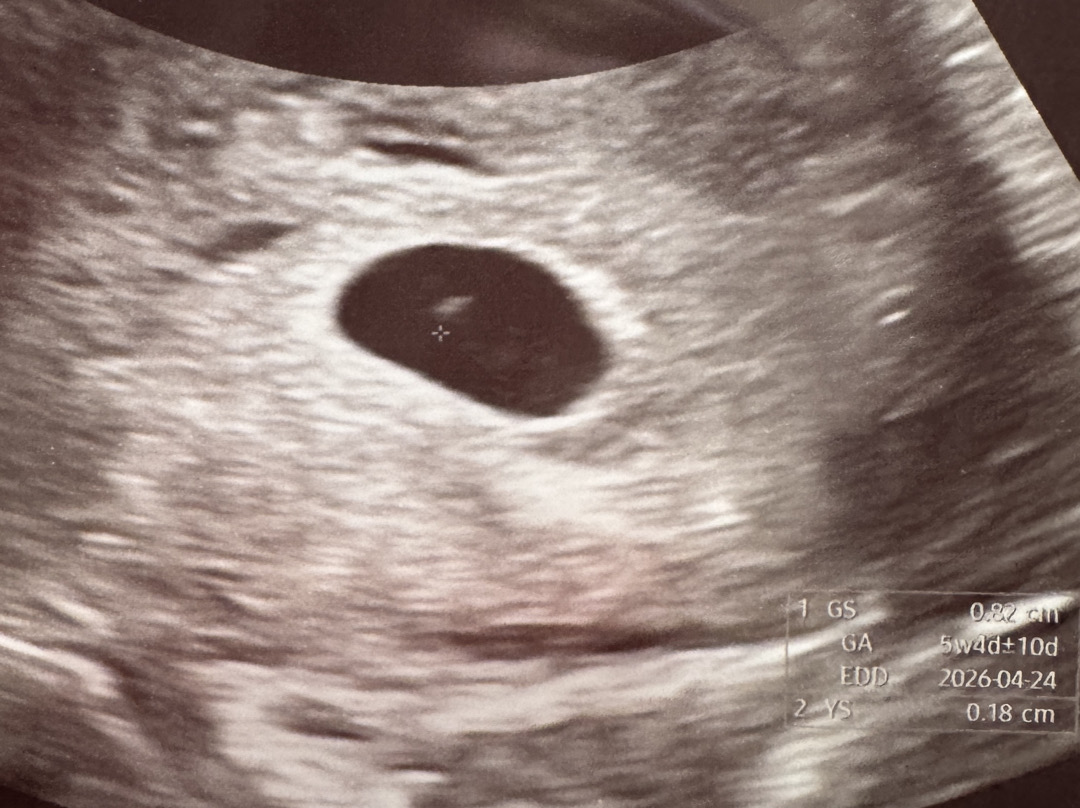

드뎌 첫 초음파!!

예상주수랑 잘 맞게 성장중이에요 ㅎㅎㅎ 제발 이대로 건강하게 만나자💕